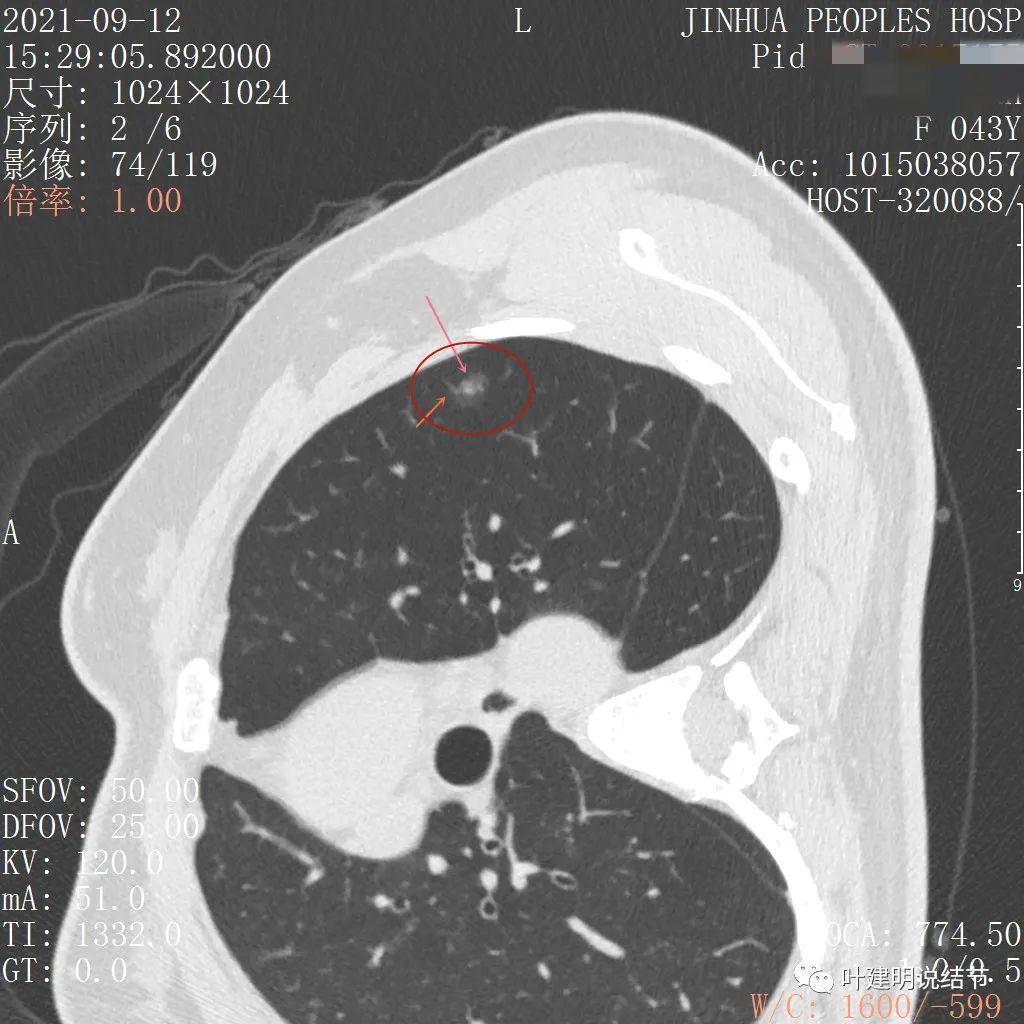

可见左肺上叶磨玻璃结节,边缘略显模糊,瘤肺边界不是很清,但总体上看,病灶轮廓仍是较为清楚的,而且有所层面有微小血管进入,病灶密度也不均匀,感觉有点杂乱。这种病灶如果随访了2个多月仍持续存在,也没多少变化的话,基本上要考虑肿瘤范畴的结节。为了看细节,我们建议其再查了靶扫描,图像如下:

病灶密度较低,膨胀性略,瘤肺边界在靶扫描上还是显得有些清晰的

病灶瘤肺边界清,密度偏低,有点散,但有微小血管进入(桔色箭头)